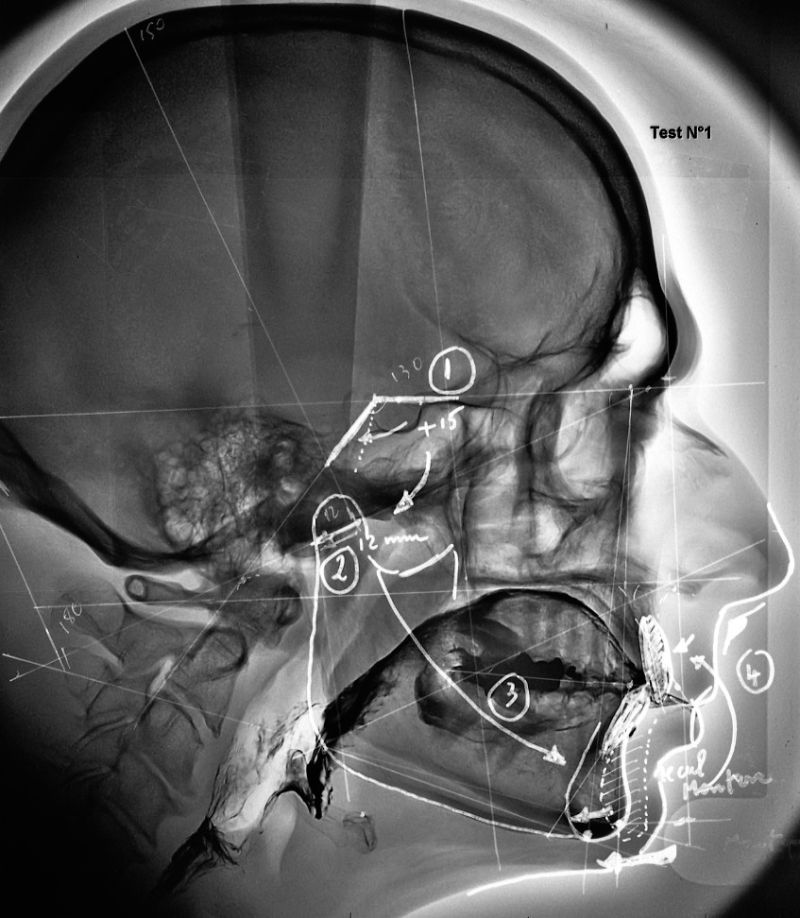

32-On pense que le volume de la langue est toujours adapté à celui de la cavité buccale